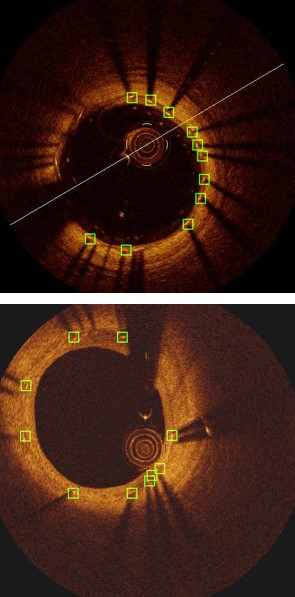

Accurate assessment of neointimal coverage after stent implantation in intravascular optical coherence tomography (IVOCT) images is important to ensure the safety and efficacy of the Percutaneous Coronary Intervention procedure [8]. Unfortunately, manual assessment requires the detection and analysis of thousands of struts within the stent, which is a challenging, tedious and time-consuming task. As shown in Fig. 1, the stent struts are small, and the visual characteristics of the region covering the thick intima (innermost layer of the artery) may make the struts inconspicuous.

Refer to caption

Figure 1: Common vascular features in IVOCT images. The middle image (c) shows the manually labeled stent struts (12 in total), with two green bounding boxes of struts (a) and (b).